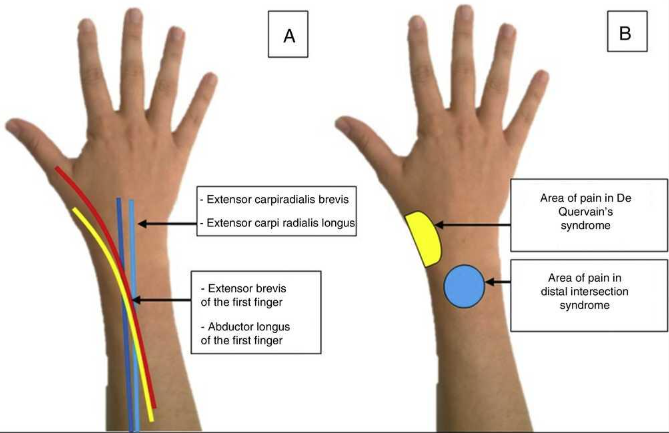

Syndrome de l’Intersection Distale

- Du aux mouvement repetés

- Croisement des 2e et 3e compartiment (Extenseurs du Carpe Vs Long Extenseur du Pouce)

- Se fait 4cm plus bas que le tubercule de Lister (bien couvrir sur IRM !)

- Oedème Péritendineux (pas dans la gaine)

Tenosynovite de la jeune maman (de Quervain)

- Ténosynovite du premier compartiment

- Mères qui portent leur enfant ++

- Inflammation des tendons au niveau de la styloide radiale